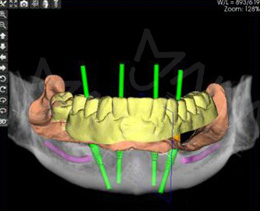

• 通过Master Force模拟前牙压低三类方案、讲解拔除前磨牙病例A7方案的核心设计理念,结合设计的6项实验,证实MasterForce对隐形矫正方案 设计优化的显著效果。

正畸治疗的关键在于诊断、及对治疗结果的预测。麦芽口腔数字化正畸科认为,当口内数据量化到毫米级甚至微米级,最有利医生对方案作出精准判断与调整,所以成功落地深圳首家全数字化口腔正畸科室,致力更严谨、精准、精密的矫牙疗效!

• 正畸专利设计软件

48小时出具动画方案不必苦等1个月

• 数字化3D打印技术

精准高效表达矫治力个性与精度结合